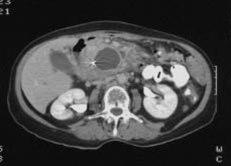

CT bilder er svarthvite. Organene fremstilles i ulike grader av grått. Vev med lav tetthet, f.eks. luftfylte hulrom, vises som mørke eller svarte partier. Vev med høyere tetthet vises i lysere gråtoner. Jo høyere tetthet, jo lysere. Beinvev fremstilles hvitt.

Akutt betennelse i bukspyttkjertelen kan i noen tilfeller vise forandringer på CT. Bukspyttkjertelen er ofte forstørret og kan ha uskarpe konturer. Ved alvorlig betennelse kan større væskefyllte områder ses som uttrykk for at det foreligger abscesser - byller med ansamling av puss. Man kan også finne væskefyllte hulrom som skyldes lekkasje av bukspyttkjertel-saft, såkalte pseudocyster.

Kronisk betennelse i bukspyttkjertelen kan vises som bindevevsdannelse (fibrose), forkalkninger og pseudocyster. Forandringen kan være vanskelige å skille fra kreft.

Kreft i bukspyttkjertelen befinner seg i to av tre tilfeller i "hodet" på kjertelen - den delen som ligger an mot tolvfingertarmen. Røntgenlegen kan se fortetninger som endrer omrisset av kjertelen. Bildene blir tydeligere etter innsprøyting av kontrast i blodet. Undersøkelsen kan også vise om det er innvekst i naboorganer, eventuelt om det er spredning til leveren.